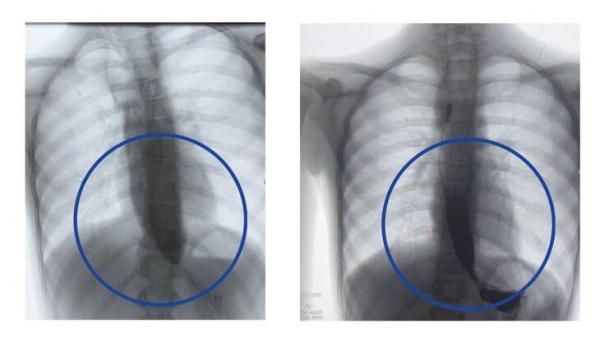

Девятилетняя девочка поступила в медучреждение с редким заболеванием – ахалазией кардии, из-за которого ее пищевод был расширен почти до 4 сантиметров, когда в норме его диаметр составляет от 7 до 10 миллиметров.

Данная процедура, по его словам, уже доказала свою эффективность у взрослых, однако в детской практике применяется редко. Тем не менее операция прошла успешно, благодаря чему контрастное исследование подтвердило свободное прохождение пищи в желудок уже на следующий день.